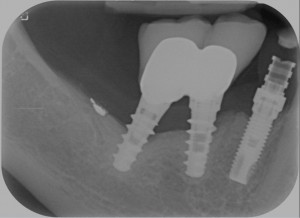

Questo problema si chiama perimplantite. Una vota si mettevano pochi impianti, il tutto veniva fatto in modo molto attento, su pazienti selezionati. Oggi invece gli impianti non si negano a nessuno, li mettono tutti, comprando quelli che costano meno e si fa a gara a chi li fa con il setting meno sterile possibile per dimostrare che si è fighi e funziona lo stesso. Poi sopra ci si mettono le cose più improbabili… guarda qui cosa mi capita di svitare da impianti messi da colleghi pochi mesi fa

Ed ovviamente non si fa alcuna preparazione parodontale perché il paziente ha pochi soldi ed “è già tanto se riesce a pagarmi la vite!”.

Tutto questo porta a percentuali di perimplantite che a 5 anni superano abbondantemente il 10%.